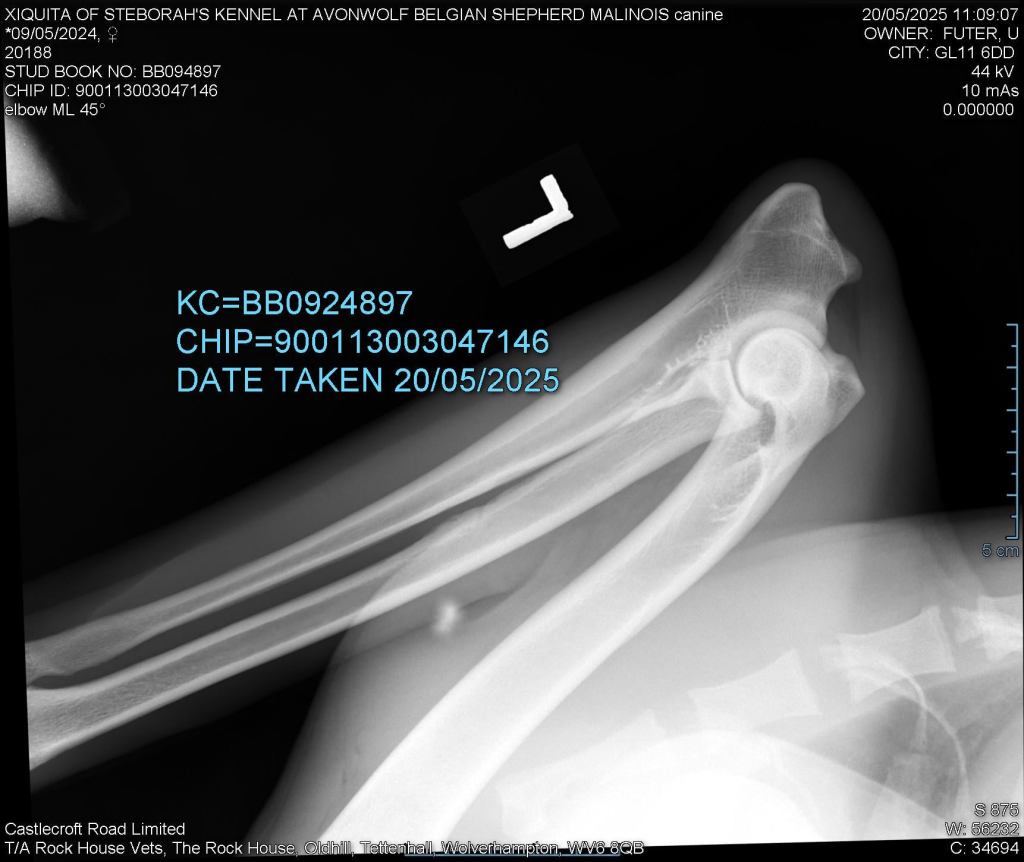

Elbows 0/0